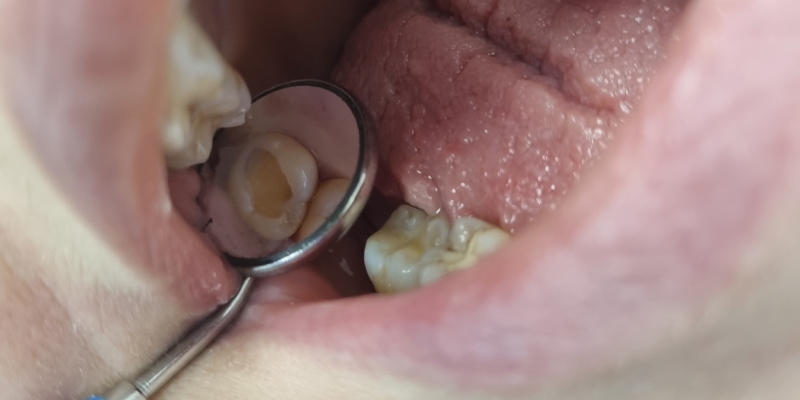

В «Стоматологию Комфорта» обратился пациент с жалобами на кариес. В ходе осмотра врач Серебрякова Мария Борисовна выявила хронический средний кариес зуба 17. Визуальное обследование показало небольшой кариозный участок. Реакция на зондирование была малоболезненной, однако эмаль имела пористую и шероховатую поверхность. Дентальное обследование показало, что ткани дентина под эмалью значительно поражены. Было принято решение о лечении кариеса и установке композитного материала Estelite А3.

В основе композитного материала Estelite – кремниево-циркониевый наполнитель, который обеспечивает высокую механическую прочность пломбы. Раствор равномерно заполняет полость в дентине и дает минимальную усадку за счёт микрочастиц одинакового размера. Пломба отлично маскирует любые объемные и сквозные дефекты, устойчива к истиранию и не выделяется на фоне натуральной эмали зуба. Материал затвердевает под действием света в три раза быстрее многих композитов, традиционно используемых для пломбирования.